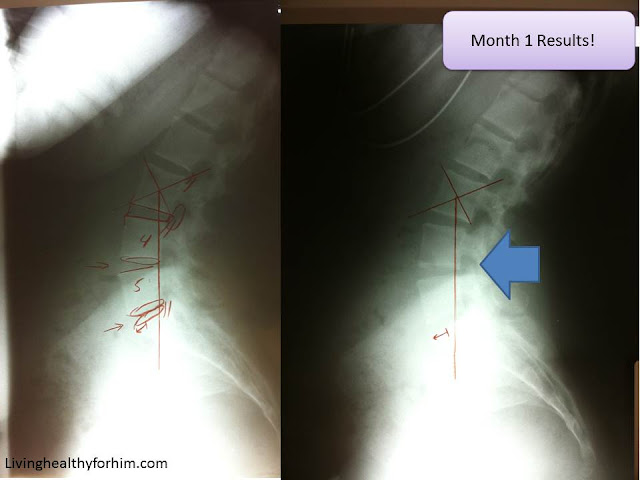

Now my neck has a different story to tell. It is making progress, but with it comes a price. First, looking at the initial x-ray on the left, you can see that my neck is curving the complete opposite way from the normal C shape that the neck should have. But in my second x-ray, you can see it is ever so slowly trying to curve the correct way. Come on cervical vertebrae! You can do it!